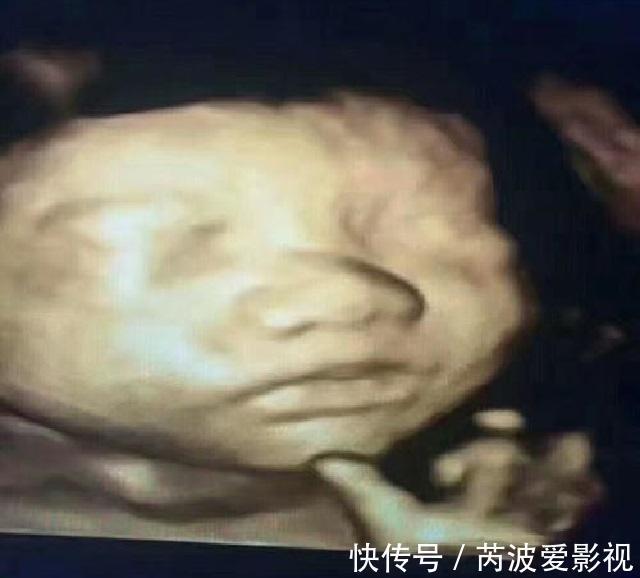

信号一、配合拍照的宝宝在怀孕20至28周之间,孕妈都会为宝宝做一次四维彩超,大排畸做完之后,都会选择为宝宝留几张照片。这个时候胎儿的不同就会显现出来,有的宝宝会安静的配合拍照,而有的宝宝会活跃的在羊水中游来游去。小欣怀孕六个月了,去做四维彩超时发生了一件奇怪的事情。

文章插图

做完大排畸后,想给宝宝拍几张照片,可宝宝的脸一直朝后,怎么也拍不到正脸。这时,医生安慰小欣说:“你可以慢慢的抚摸肚中的宝宝,然后试着跟他沟通。”半信半疑的小欣想:这么小的宝宝怎么能听懂话呢?不过也没有更好的办法,只好试试看了。令人意外的是宝宝竟然神奇地转了过来,食指和中指还淘气地比了一个剪刀手。看到这个场景,医生一边拍照,一边微笑着说道:这是一个聪明宝宝。小欣问医生为什么?